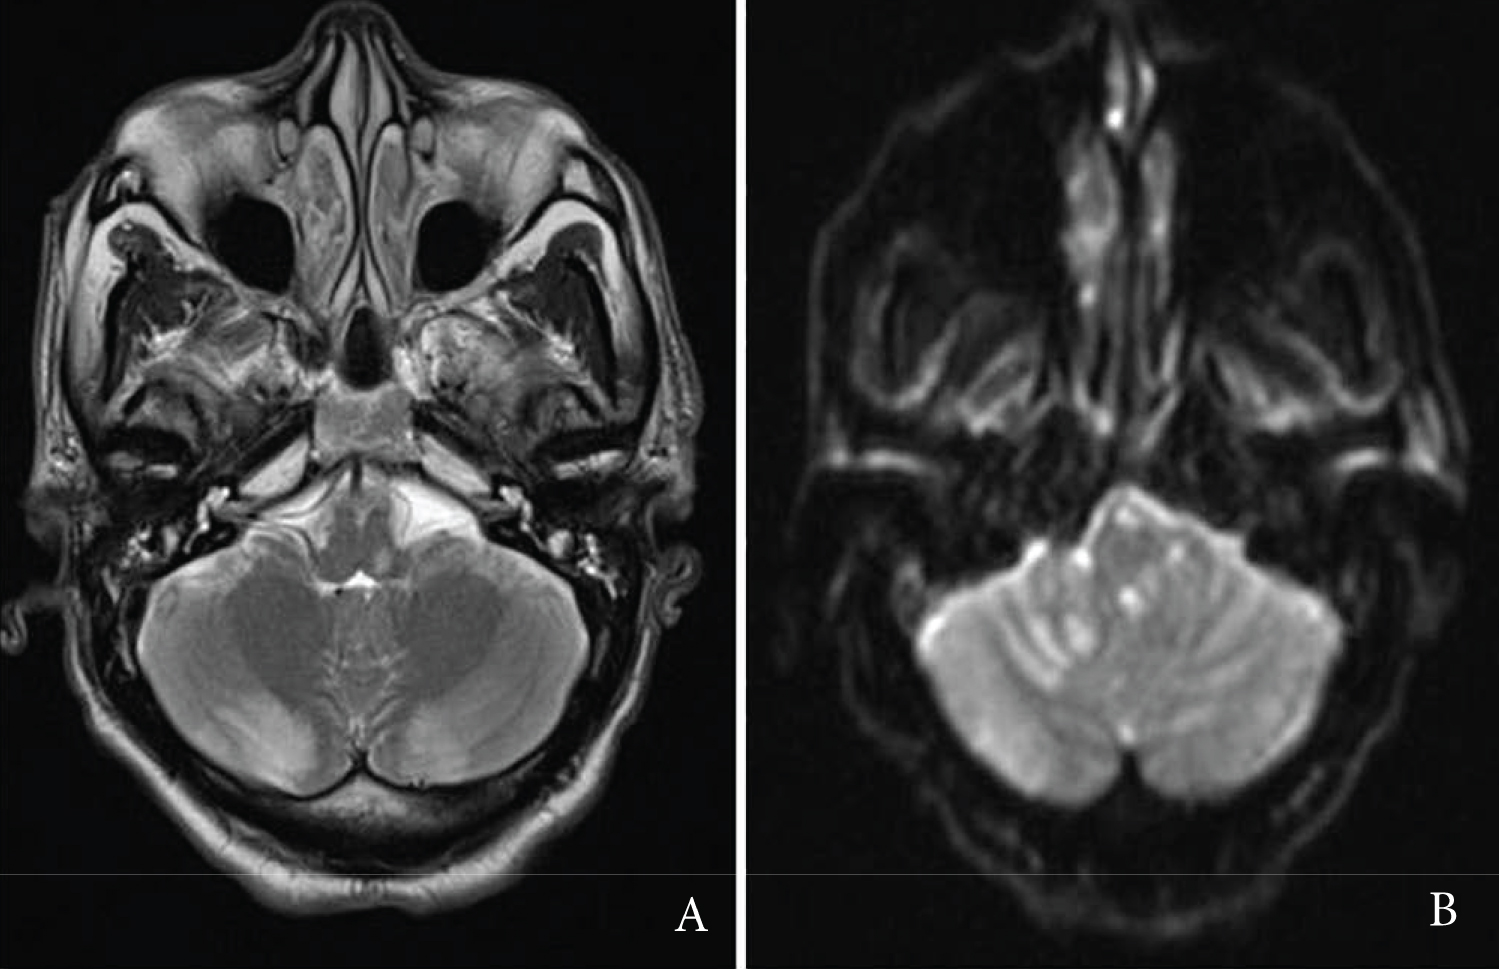

A 47-year-old male presented with sudden onset of severe dizziness, nausea and vomiting, and profound ataxia. Initial MRI brain demonstrated a hyperintense lesion on the left side of the medulla secondary to infarcts in the left posterior inferior cerebellar artery (PICA) and anterior inferior cerebellar artery (AICA) territories, and a thrombosed aneurysm of the left vertebral artery (Figure 1). He was GCS 15 on arrival and admitted to the ward. Three days later he had a sudden drop in GCS to 10. Urgent CT brain demonstrated a hypodense left cerebellar lesion and compression of the fourth ventricle with tonsillar herniation. Subsequently, he underwent an urgent SDC with EVD insertion and resection of necrotic cerebellar tissue.

Figure 1: A) T2-weighted MRI axial slice demonstrating left-sided inferior cerebellar infarction; B) Corresponding T2-weighted MRI coronal slice. View Figure 1